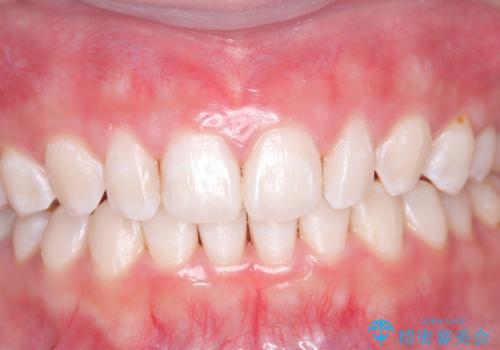

最新の症例

Latest cases